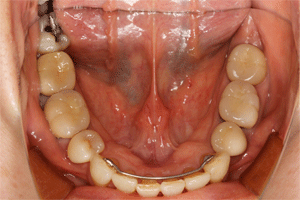

| 全顎的に治療しました

左が術前、右が術後です。前歯でかみ切りにくかったそうですが、改善したそうです 見えるところはセラミックで、見えないところはメタルで修復しています 右下の親知らずを保存不可能で抜歯していますが、咬むのには問題ないそうです 右上の咬合痛が主訴で来院されましたが、まだ残っています 長持ちするように、2〜3ヶ月に一度のメンテナンスを行っていきます |

上下の被せものの治療の場合、通常下顎からおこなうのですが、今回は上顎から治療をおこなっていきます 古い被せものを外して、根の治療、土台の治療で、右下の一番奥の歯が抜歯となってしまいました。親知らずの歯です。1本なくなってしまいましたが、咬むことには不自由がないとのことでした。 上顎治療後、下顎の治療をしていきます。 |